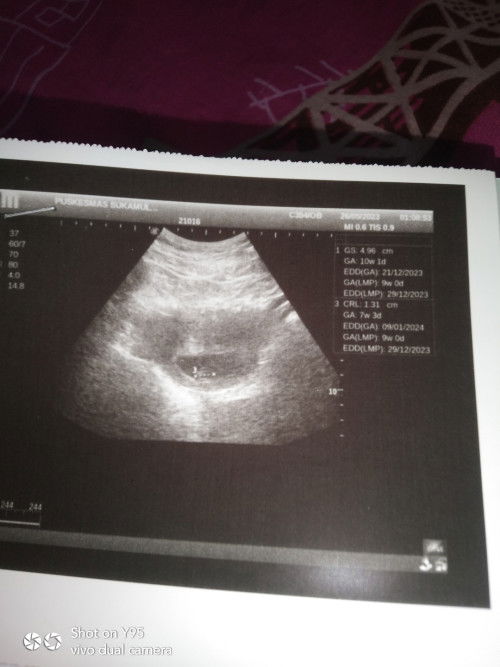

Usia Ukuran kantong dan usia janin tak sesuai

Bun barusan saya Usg ke puskesmas,pas usg kata dokternya ukuran kantong udh 10 minggu tpi ukuran janinnya baru 7w 3d ,apa itu normal bun,dispuskesmas emg gabisa cek djj,mknya sruh ke spesialis jdi kepikiran gini#bantusharing #ingintahu